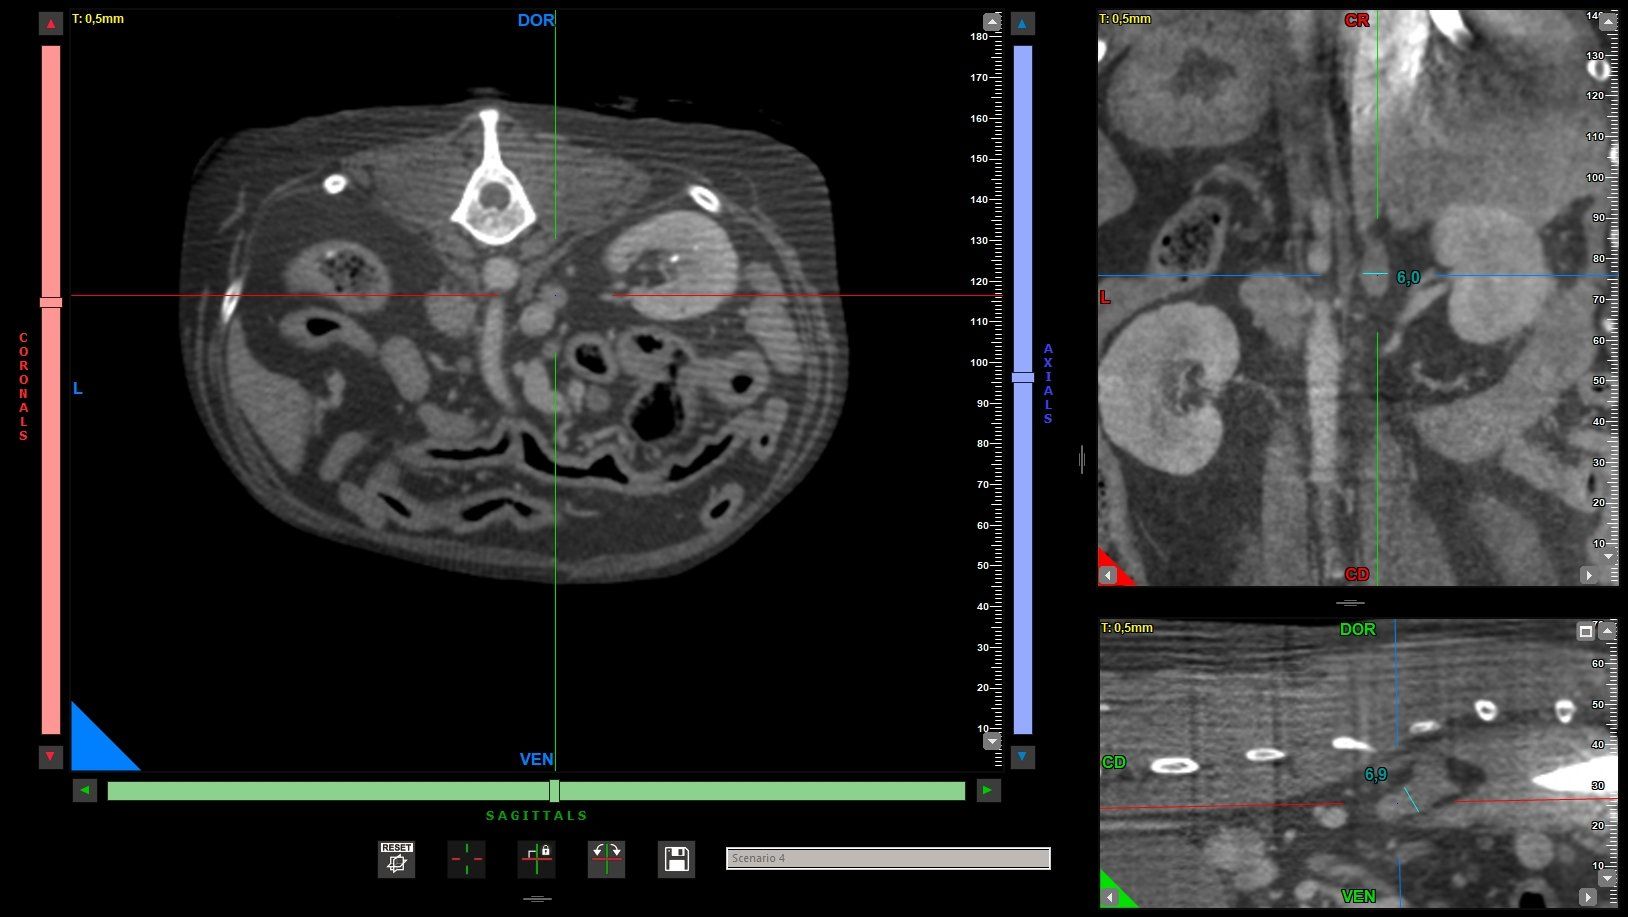

Tra i servizi che l’Ospedale Veterinario Città di Conegliano fornisce, non mancano quelli di diagnostica per immagini:

ecografia, radiologia digitale, TC.

Gli specialisti Roberto De Pellegrin e Riccardo Pelizzon, in particolare, si occupano degli esami ecografici, ecocardiografici, tomografici per l'acquisizione di immagini del corpo del paziente attraverso l'esposizione a ultrasuoni o a raggi X.